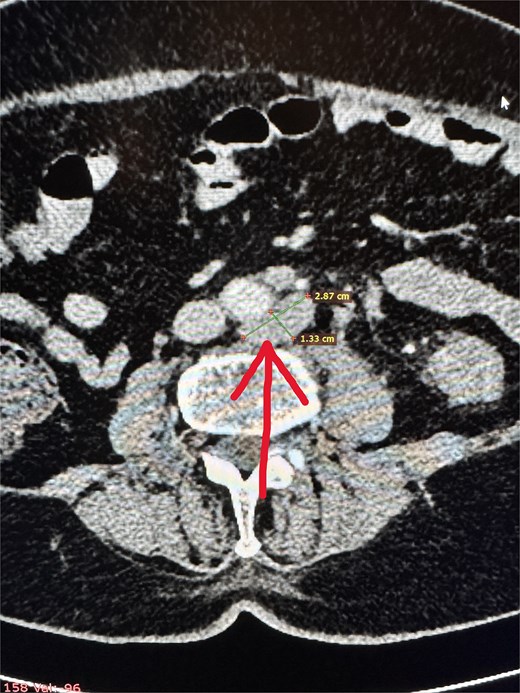

two cystic lesions on the periphery of the pancreatic tail, up to 7 mm in diameter, and one cystic lesion in the area of the pancreatic head and body (~10 mm),

predisposition resulting from small pancreatic cysts detected on CT imaging.